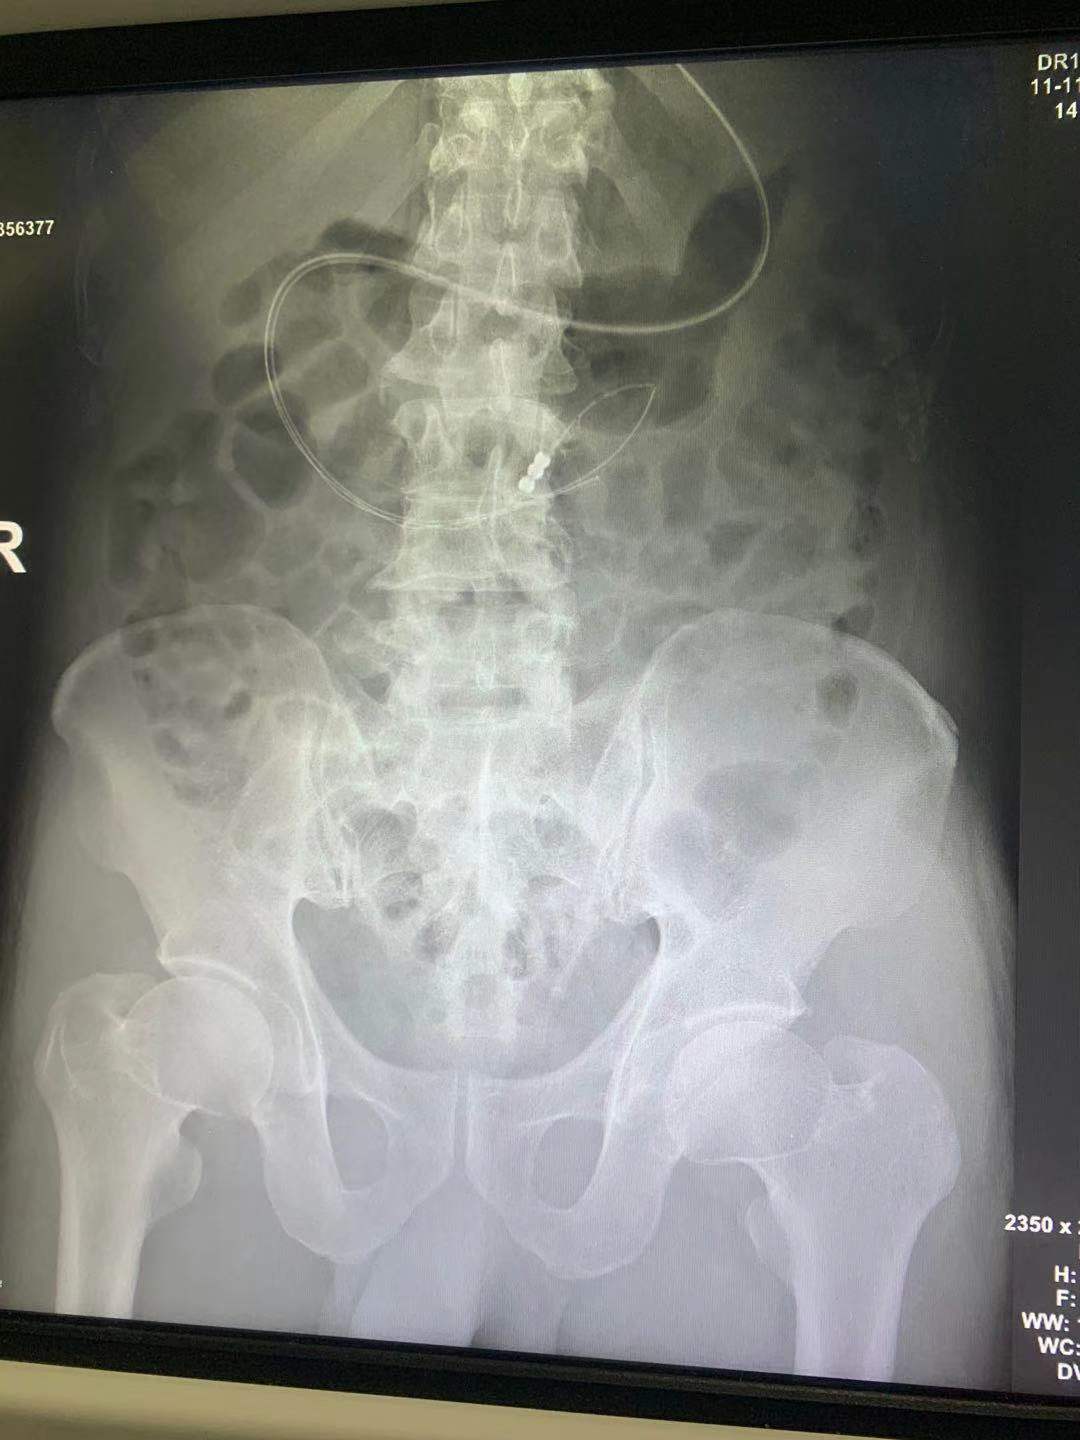

X线片显示置管成功

在科室领导的带领下,重症医学科医护团队共同为患者实施经鼻空肠营养管置入术。由莫叶秀医师及张佳佳护士相互配合,按照留置胃管常规置入约55厘米后,注入少量空气,用听诊器听诊腹部有气过水声,证明置管已顺利到达胃部,随后通过听诊器听诊判断置管位置,并结合患者体位继续将管道缓慢轻柔随肠蠕动推入……约半个小时,长度约105厘米的空肠营养管成功置入患者空肠,置管过程十分顺利。随后泵入肠内营养液,患者无任何不良反应。之后,患者接受经鼻空肠管营养支持,病情逐步改善,目前已转回当地医院继续治疗。